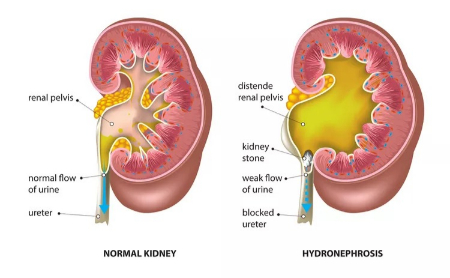

استاز کلیه به حالتی گفته میشود که جریان ادرار در کلیهها یا حالبها (لولههایی که ادرار را از کلیه به مثانه منتقل میکنند) به دلیل انسداد یا کاهش تحرک متوقف یا کند میشود. این توقف میتواند باعث تجمع ادرار در کلیه (هیدرونفروز) و فشار بر بافتهای کلیه شود، که در نهایت ممکن است به آسیب کلیوی منجر شود.

استاز کلیه به توقف یا کاهش جریان ادرار در کلیهها یا حالبها اشاره دارد که معمولاً به دلیل انسداد ایجاد میشود. ورم کلیه (هیدرونفروز) زمانی رخ میدهد که انسداد باعث تجمع ادرار و تورم کلیهها میشود. دلایل شایع این مشکلات عبارتاند از:

• سنگ کلیه: تجمع نمکها و مواد معدنی در ادرار که سنگهای کوچک و سختی را تشکیل میدهند و میتوانند در کلیه یا حالب گیر کنند.

ورم کلیه (هیدرونفروز) زمانی رخ میدهد که انسداد باعث تجمع ادرار و افزایش فشار بر کلیهها میشود، که بهمرور زمان میتواند به بافت کلیه آسیب برساند. شدت علائم به مدت زمان انسداد بستگی دارد. علائم شایع عبارتاند از: